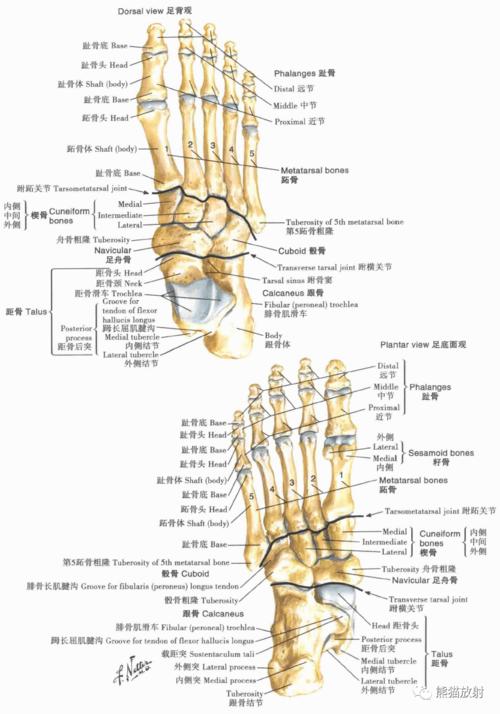

足x线解剖图,足正侧位x线解剖图

超清晰的下肢小腿踝与足解剖图

x线高清图谱 | 精致足部解剖

足解剖图名称图解

足骨x线解剖图

足解剖图

足背解剖图